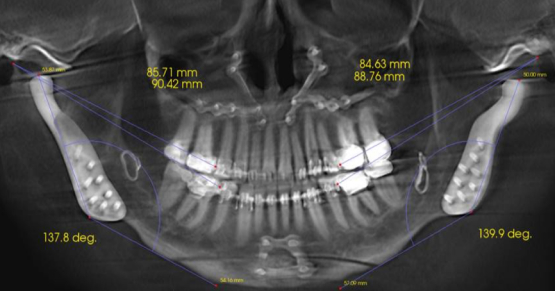

Abfraction (Stress)

The traditional abfraction theory postulates that upon occlusal loading, the cervical area of the tooth becomes a fulcrum. This action leads to tensile stress which leads to disruption of the enamel’s brittle crystalline structure. Repeated loading eventually causes enamel to break away from the margin (12).

While this theory is logical, it is controversial among dentists and researchers. Several finite element analysis (FEA) studies and clinical trials have supported this theory, while systematic reviews have not demonstrated a clear association (13-19). Some clinicians treat patients with occlusal adjustments and full-mouth equilibration to manage NCCLS. However, considering the controversial nature of the evidence, more information may be needed to support this irreversible treatment strategy. The literature lacks a high-quality prospective clinical study that may elucidate the controversy surrounding the etiology of abfraction lesions.